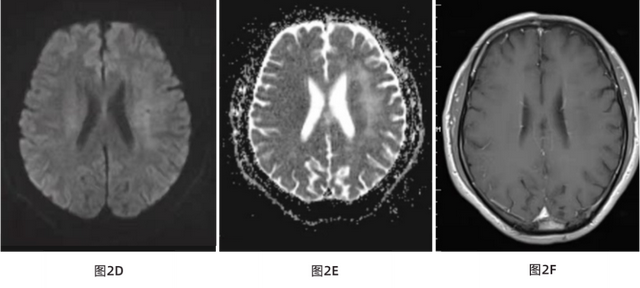

图1 A T1WI矢状位前额局部头皮脂肪层变薄、消逝 (如图红色箭头所示);图1B T1WI冠状位左前额局部头皮脂肪层变薄、消逝 (如图红色箭头所示);图1C T2WI轴位左前额局部头皮脂肪层变薄、消逝 (如图红色箭头所示)